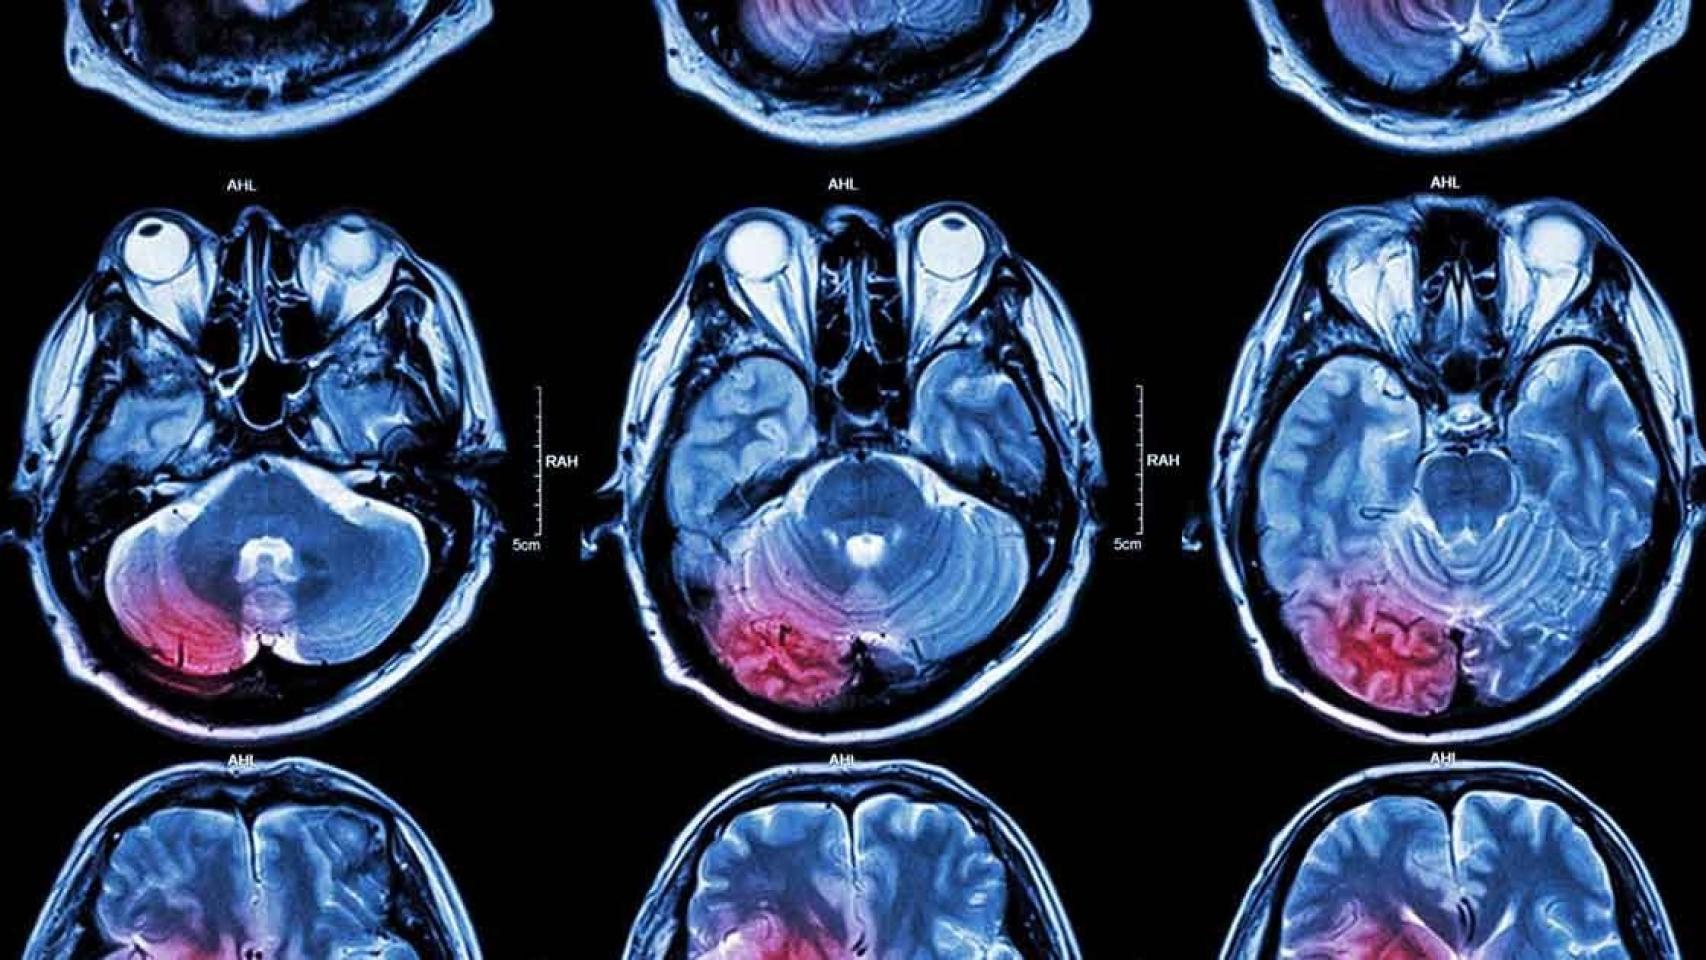

La acumulación de amiloide en los vasos sanguíneos es algo que se puede detectar mediante resonancia magnética, pero habitualmente no se tiene en cuenta. "Hay algunos tipos de secuencias que permiten ver el grado de fineza de los vasos", comenta Guillermo García Ribas, neurólogo del Hospital Universitario Ramón y Cajal.